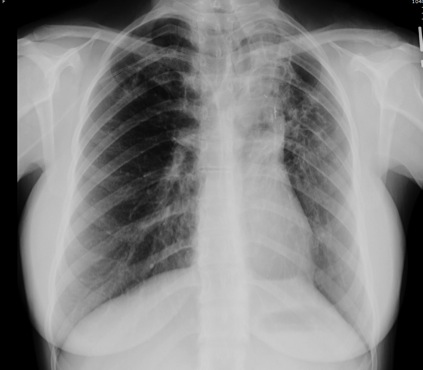

Figure 2: Chest computed tomography showing bronchiectasis and right upper lobe opacity suggesting the site of bleed